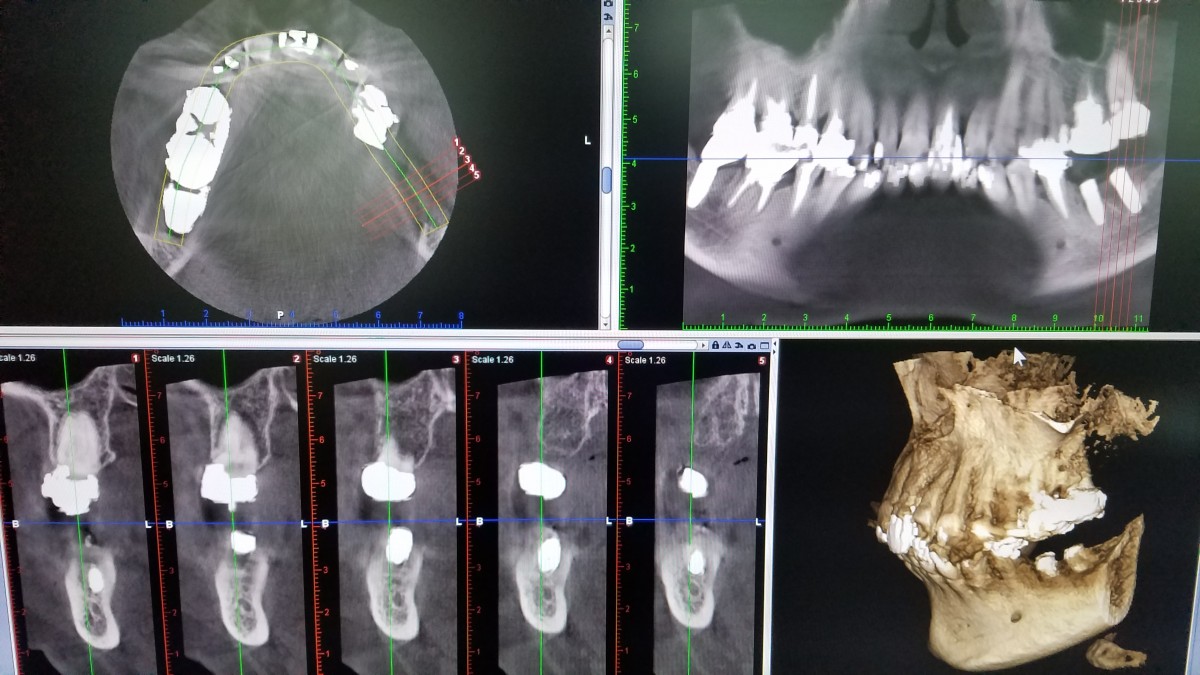

従来のデジタルでの全顎の2Dのパノラマ撮影に加え、多方向からの3D画像を撮影できる口腔内専用のコンビームCTを完備しております。病巣や歯根の状態、インプラント治療における正確な診断が可能になりました。

レントゲンの画像をモニターに大きく映してわかりやすく説明致します。